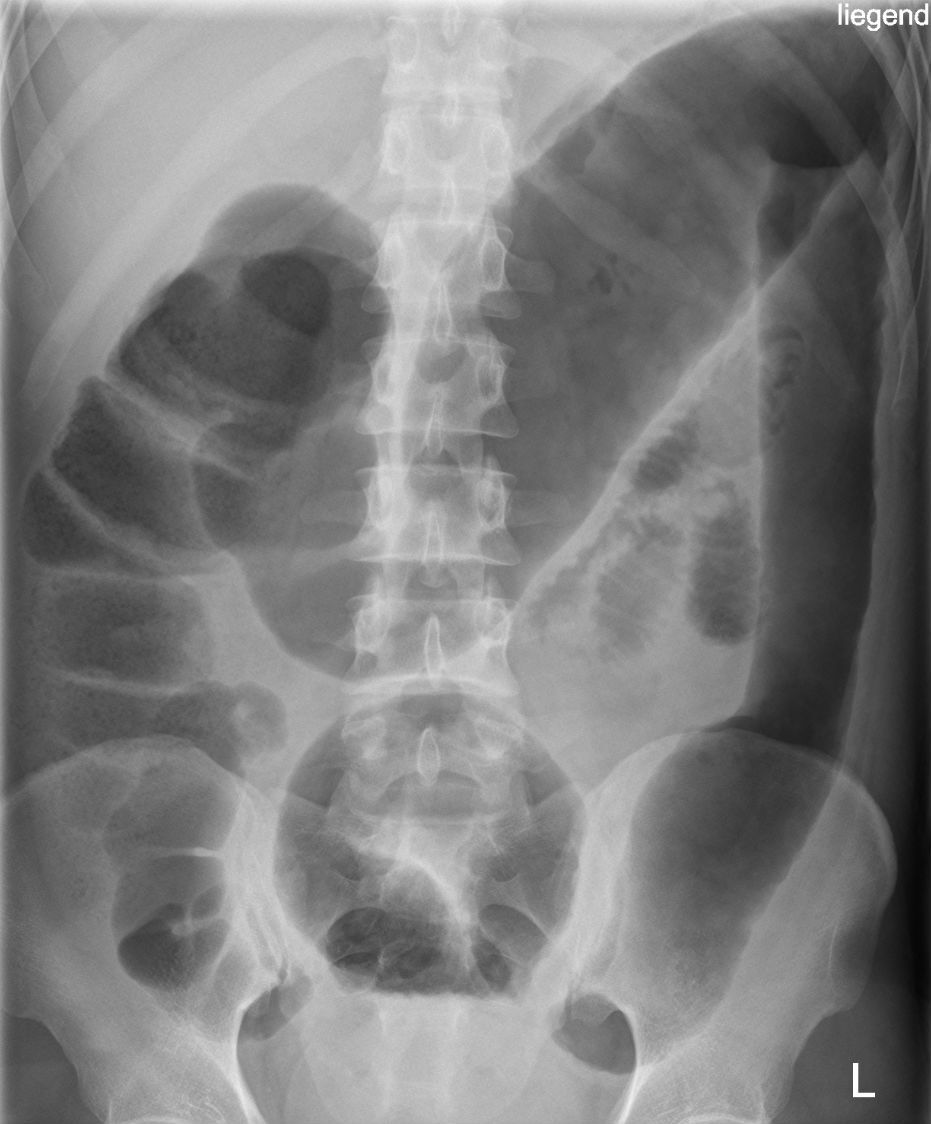

Q

what does this AXR show?

A

large bowel obstruction

- peripheral bowel loops

- large dilated bowel loops >6cm diameter

- haustra partially crosses diameter of bowel